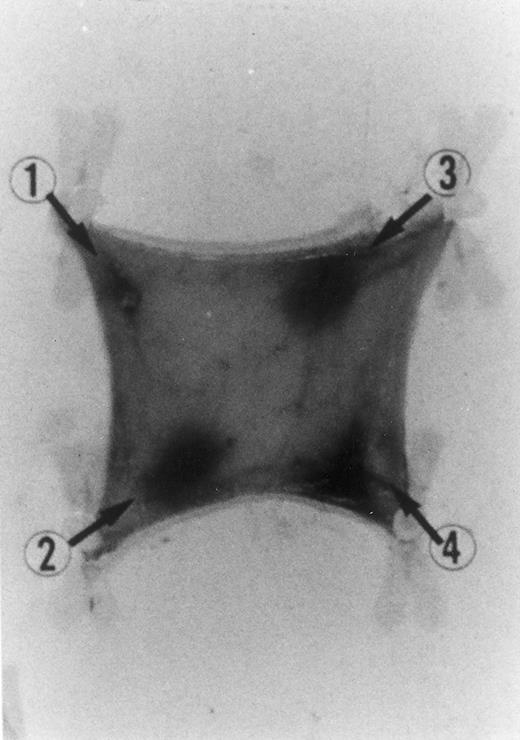

Evan's blue-stained intradermal injection sites showing the kinetics of the dermal inflammatory response to exogenous human recombinant RANTES 20 ng/50 μL (no. 2) and 10 ng/50 μL (no. 3); while PBS 50 μL was a negative control (no. 1) and LPS 10 ng/50 μL is a positive control (no. 4). This representative experiment was found to be reproducible and has been performed at least three times.

In Fig 2 we show the histologic results of a representative experiment (N = 12 rats) 4 hours after intradermal injection (50 μL) of LPS (10 ng), RANTES 20 and 10 ng, and PBS (control). This figure shows that while PBS (injection site no. 1) does not produce any appreciable effect, LPS (10 ng/50 μL, injection site no. 4) and RANTES (20 ng, site no. 2; and 10 ng, site no. 3) produced a marked enlargement of dye effusion.